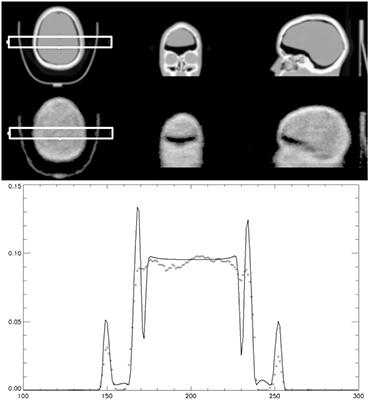

Figure 3 demonstrates that the scaling of the reconstructed attenuation map from the transmission data from Lu-176 is similar to that derived from a CT scan. There is a loss of fine structure detail using the transmission method. How this translates into PET emission data corrections will be investigated.

Figure 3. CT and scaled attenuation map from transmission from Lu-176 with 1 h acquisition (top) of a striatal brain phantom. Profiles (bottom) from the attenuation map created by the CT (-) and from Lu-176 transmission (◊) are compared.

Work was performed to show the PET reconstructed images if the attenuation maps from the simultaneous transmission scan were used for the corrections to the PET emission data. The first case was a striatal head phantom with a fillable water cavity for addition of activity to the phantom. The phantom was filled with 4 mCi of F-18 and placed in a carbon fiber head holder. The phantom was scanned using a standard head-neck protocol for duration of 10 min. A corresponding CT was performed before the PET scan was acquired. The PET scan was the same for all three cases where the emission data was rebinned for 10 min into time of flight sinograms. Transmission based attenuation maps were reconstructed with a blank scan with duration of 36 h and the same reconstruction protocol used in the cold human studies above. Figure 9 shows three cases of interest, CT corrected, 1 h Lu-176 transmission and 10 min of Lu-176 transmission data. The 1 h collect of Lu-176 data was performed to show the quality of the method with higher statistics and compare it to a more reasonable time for patient studies. The attenuation correction and scatter corrections were performed using the associated attenuation map and the PET emission reconstruction performed was OP-OSEM with time of flight using 2 iterations and 24 subsets.

Figure 9. Attenuation maps derived from CT (top left), 1 h of Lu-176 transmission data (middle left) and 10 min of Lu-176 transmission data (bottom left). Images on the right show the PET emission reconstruction of 10 min of emission data from 4 mCi of F-18 (image positions correspond with attenuation maps used during corrections and reconstruction).

Standard image High-resolution imageThe PET emission data shows little difference between all three cases. Uniformity in all three cases also shows little differences demonstrating that the attenuation maps of this simulated brain scan are good enough to perform the corrections to the emission data even with 10 min of data.